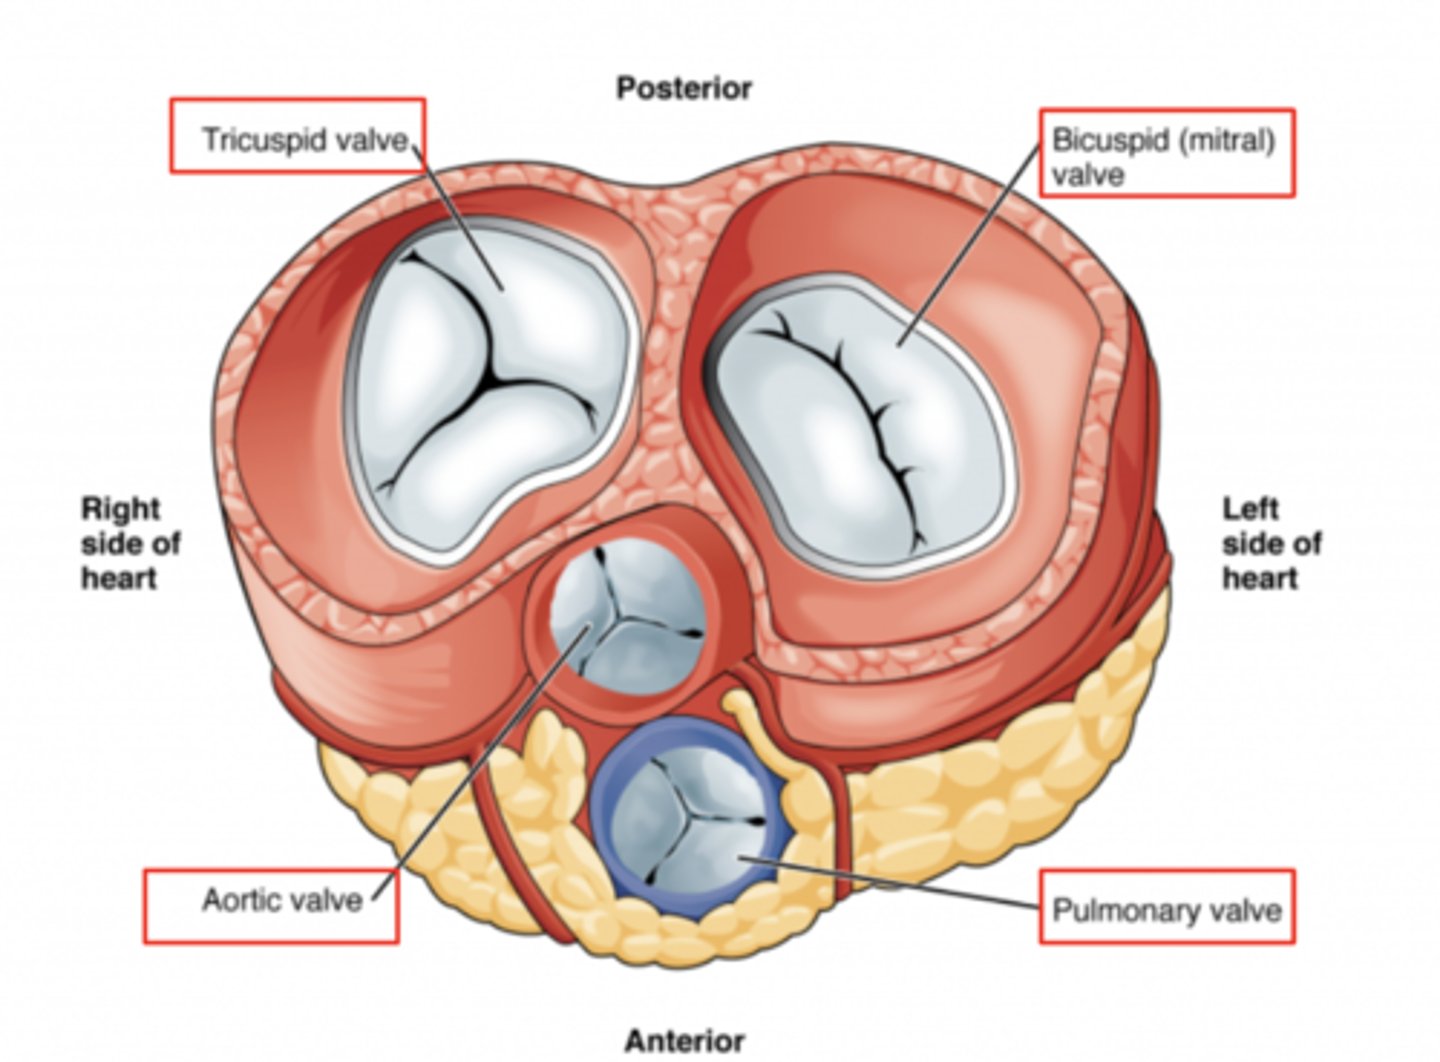

What are the valves separating atrium and ventricle?

. Tricuspid valve (right atrioventricular valve, 3 cusps)

. Mitral or bicuspid valve (left atrioventricular valve, 2 cusps)

AXIAL VIEW OF THE HEART

What are the 3 cusps of the tricuspid valve?

Anterior

Posterior

Septal

What are the positions of the pulmonary valve cusps?

Anterior

Right

Left

What are the four valves in the heart?

Tricuspid

Mitral or bicuspid

Pulmonary

Aortic

What valves are assuring the AV unidirectional flow?

Tricuspid (right)

Mitral or bicuspid (left)